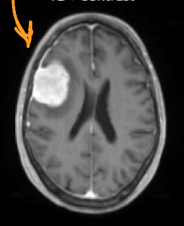

what is the diagnosis

brain abscess (with periabscess edema)

33

brain tumor